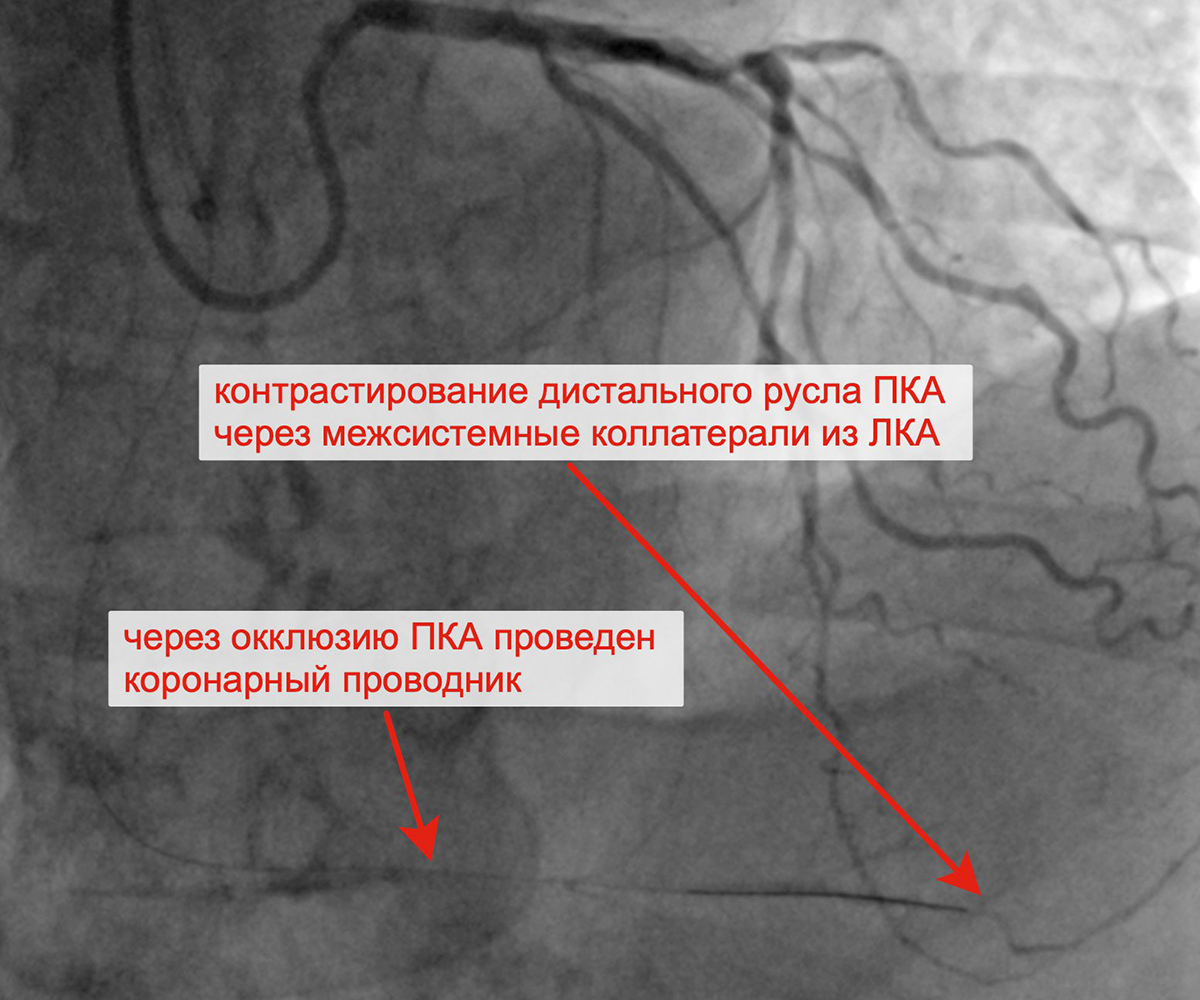

Чрескожное коронарное вмешательство (ЧКВ) на хронической окклюзии ПКА выполнялось билатеральным лучевым доступом: через левую лучевую артерию диагностическим катетером параллельно выполнялись съемки ЛКА, что позволило визуализировать через межсистемные коллатерали дистальное русло постокклюзированной ЗМЖА и контролировать процесс реканализации хронической окклюзии и проведение коронарного проводника в дистальное русло ЗМЖА. Успешно была выполнена реканализация ЗМЖА, баллонная ангиопластика и стентирование правой коронарной артерии (3 стента с лекарственным покрытием). При контрольной ангиографии: стенты и ПКА проходимы, позиционирование стентов адекватное, диссекции или остаточного стеноза в стентированных сегментах ПКА нет, кровоток TIMI 3 по ПКА и всем ветвям. Пациент был на следующий день выписан из клиники.

Хроническая окклюзия правой коронарной артерии Реканализация ПКА с контрастированием дистального русла

ПКА контрлатеральным доступом через ЛКА